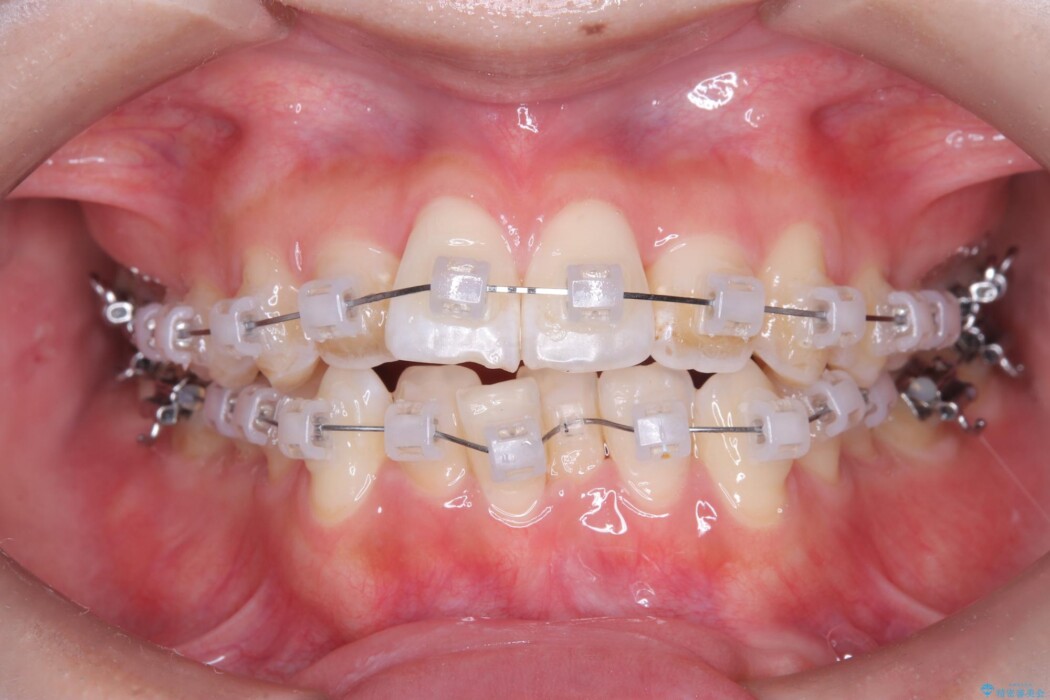

歯の移動量や力のコントロールを最適化することで、短期間で治療完了しました。

「矯正は時間がかかる」というイメージをお持ちの方も多いですが、症例によっては、非抜歯でも短期間で改善が可能な場合があります。

治療後は歯並び・かみ合わせともに大きく改善し、患者様にも大変ご満足いただけました。